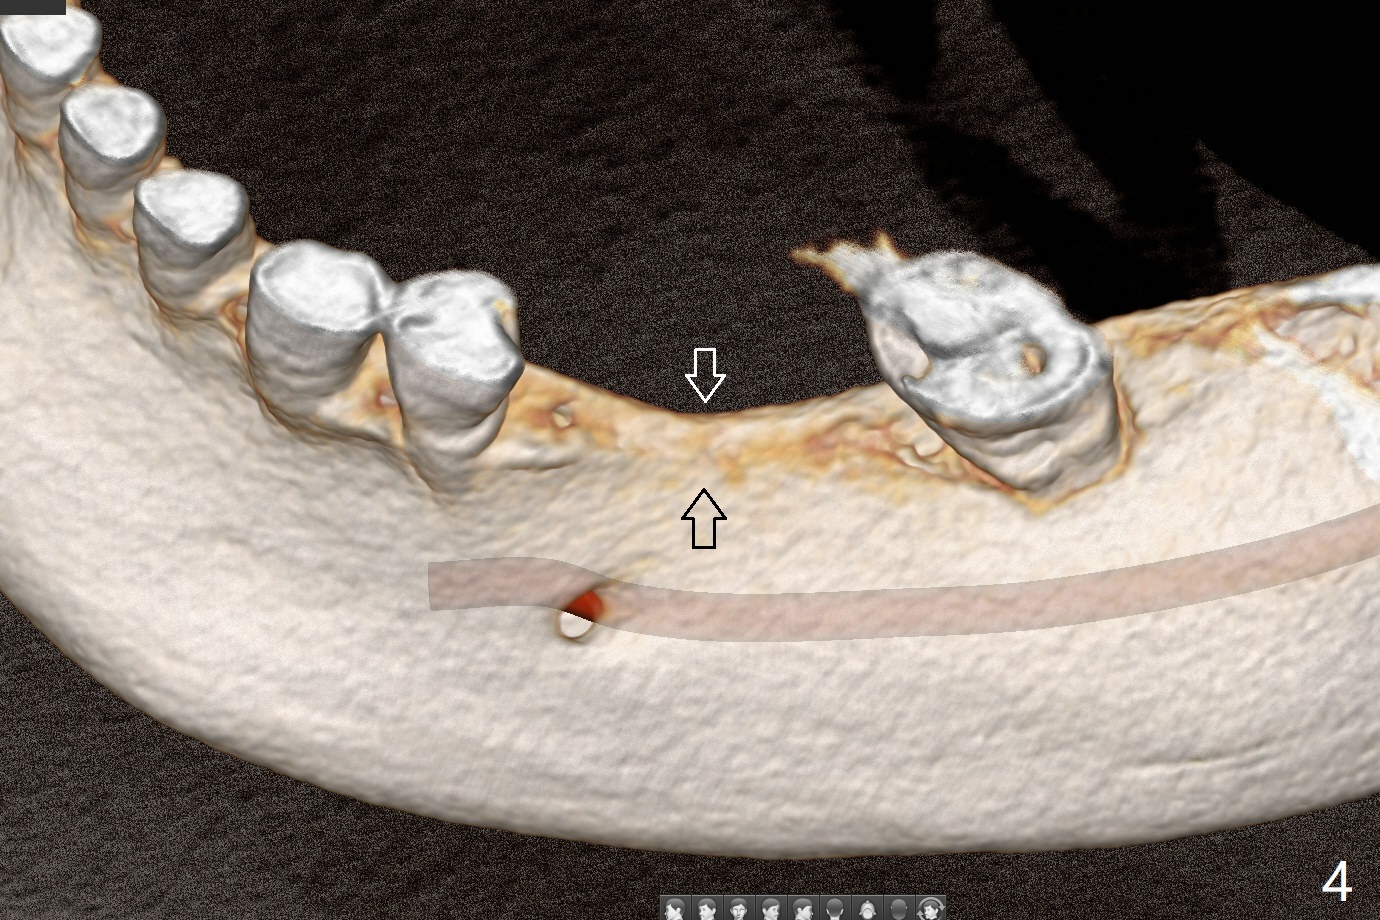

57岁女缺失四个下牙(图一),由于保险限制,先考虑左边种植(图二,三),主要问题是牙槽嵴狭窄(不过左上牙桥做的太长了,尤其是5,6(图一'),造成下面垂直距离缩短,修复困难。总之,她的牙齿显得短小)。牙槽嵴狭窄处理方法:切口,使用导板用bone trimmer和最细钻头(point drill或者2.2毫米)钻洞(图四:黑圆圈),到深度,然后用圆形骨锯在牙槽嵴顶部劈开(弯曲红线),必要时做三个垂直骨切口(图六),徒手利用旋转式骨扩张器,或者骨凿,推开颊侧骨板。也准备外科钻头(新的)。放置导板和钻头除去舌侧骨板,最后在5,6分别植入3.0 或者3.5毫米,4.0或者4.5毫米植体。如果初步稳定性好,即刻修复,主要防止7继续近中倾斜,必要时,7近中(图一*)植骨。抽血制备两个PRF膜和粘性骨块。